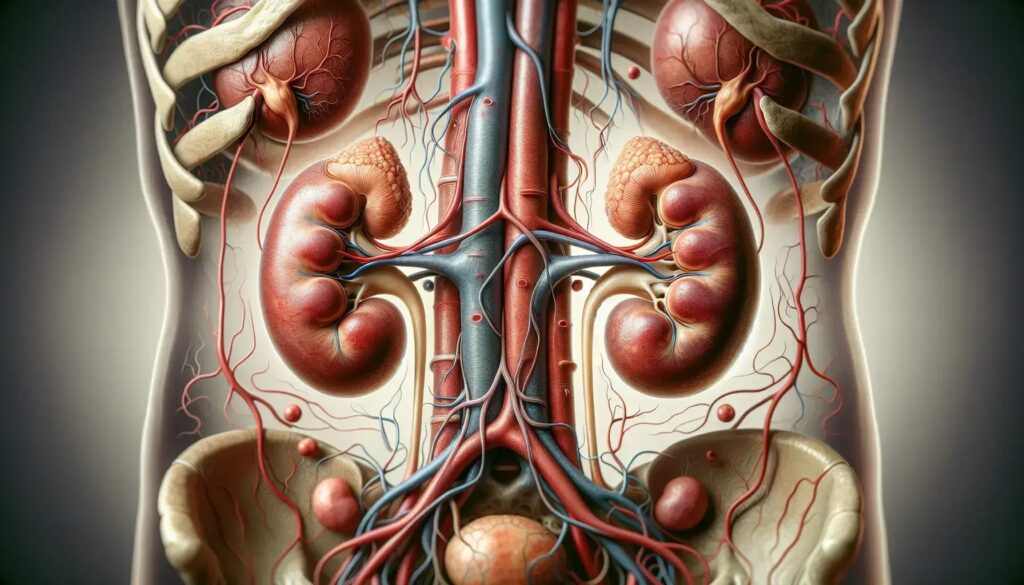

Sistema Excretor

El sistema Excretor elimina desechos líquidos y regula el equilibrio de agua y electrolitos en el cuerpo.

Componentes

- Riñones: Filtran sangre para formar orina.

- Uretra y uréteres: Conducen la orina hacia la vejiga.

- Vejiga urinaria: Almacena orina hasta su eliminación.

Funciones

- Eliminación de desechos: Excreta productos metabólicos.

- Regulación del equilibrio hídrico: Mantiene niveles adecuados de agua y sal.

- Control del pH: Ajusta la acidez sanguínea.